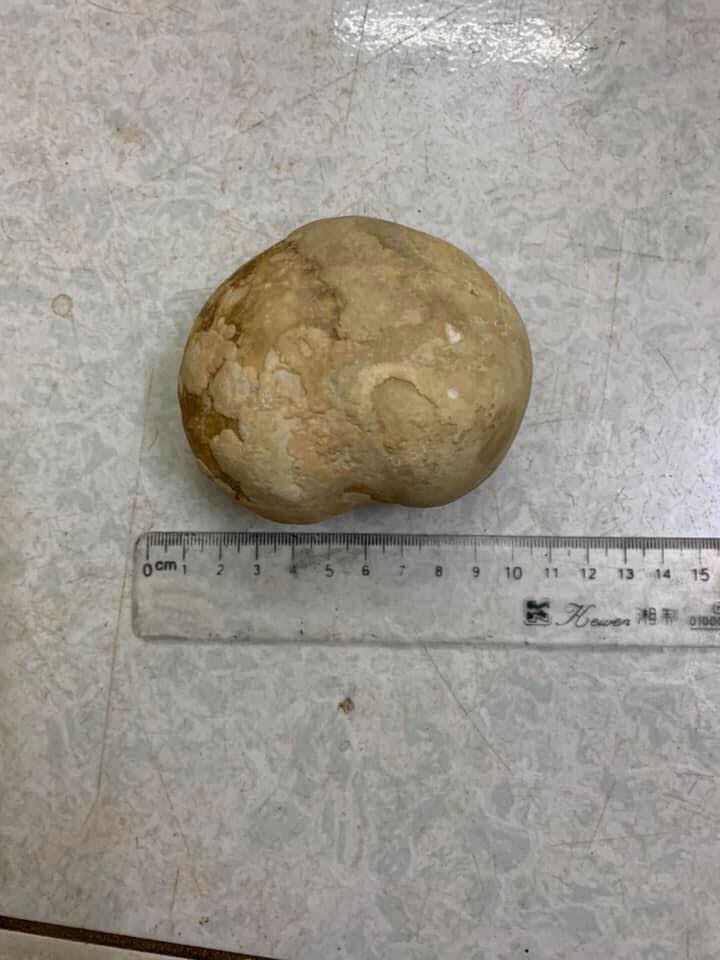

Photos of a giant bladder stone that a young woman recently had surgically removed have doing the rounds on Vietnamese social media.

Several Vietnamese media outlets have been reporting on the case of a 34-year-old woman who showed up at the emergency room of Phu Binh General Hospital, in Thay Nguyen, complaining of severe pain in her abdomen. After running some tests, a CT scan revealed that the woman had a massive, round mass in her abdomen. She was scheduled for emergency surgery, and a stone over 10-cm-long and weighing 400 grams was extracted from her bladder.

The news reports don’t offer too much information about this case, but photos include a CT scan, as well as a medical nurse posing with the giant stone. It was obviously quite a rare sight at the hospital…

According to a 2014 case report in the Turkish Journal of Urology, giant vesical calculi weighing more than 100 gm are rare, with fewer than 85 cases reported in English over the years involving a stone over 100 grams. If confirmed, this 400-gram- stone definitely qualifies as a medical oddity.

This is far from the largest bladder stone ever recorded. Back in 2016, Chinese doctors reported the case of a 54-year-old man who had a massive 1,048-gram pelvic stone in his bladder. And that was only the largest bladder stone ever recorded in China.

Photos of the 34-year-old woman’s 400-gram bladder stone went viral in Vietnam over the last couple of days, with most users expressing their disbelief about the woman’s threshold for pain.